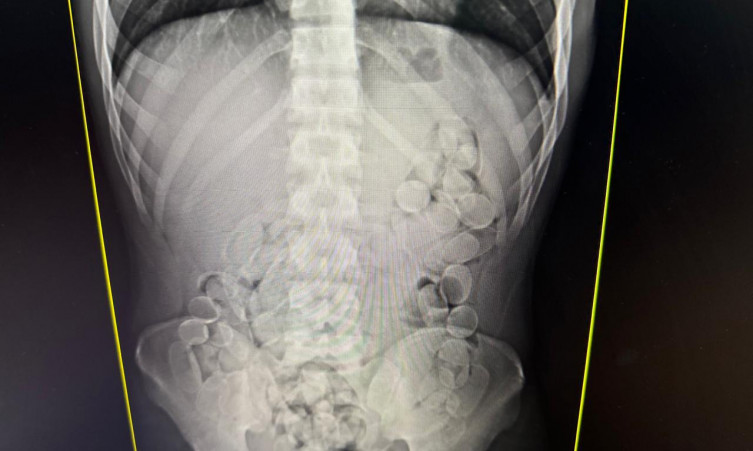

Raio-x de passageiro que engoliu cápsulas de cocaínaNesta fiscalização de bagagens, foram encontradas 50 cápsulas de cocaína e os cães farejadores indicaram a presença de drogas com mais dois passageiros. Diante da suspeita de que poderiam ter engolido cápsulas da droga, duas mulheres e um homem, foram encaminhados à Santa Casa para exames de raio-x e expelir o entorpecente. Posteriormente, os três confessaram ter ingerido aproximadamente 100 cápsulas cada um. Foram cerca de quatro quilos de cocaína apreendidos.